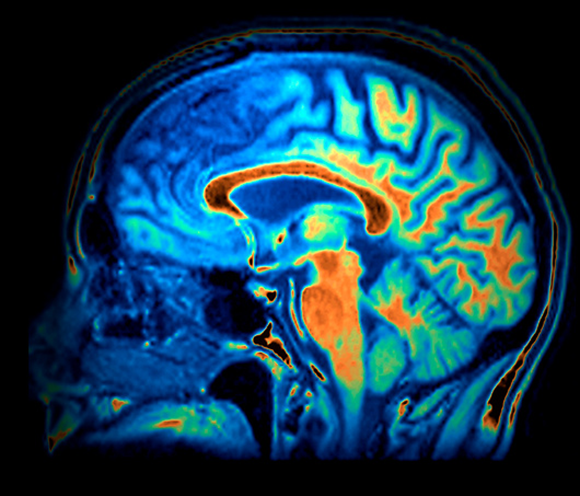

Frontotemporal dementia involves degeneration of cells in the temporal and frontal lobes. MRI scan of a patient with frontotemporal dementia.| Zephyr / Science Photo Library